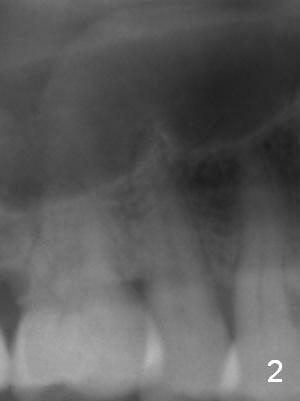

A 61-year-old man (WJ) cracked the tooth #31 after RCT. Four years after #31 extraction, the tooth #4 cracks by itself. The apex of the tooth appears to protrude into the sinus and is closely associated with the sinus septum (triangle: Fig.2,3). An implant will reach the top of the socket for stability (Fig.4 black area). The abutment is expected to be 4.8x4(3) (SM) or 4.5x4(3) (UF) mm. Metronidazole will be used for disinfection of the socket. On returning, he requests #31 implant.